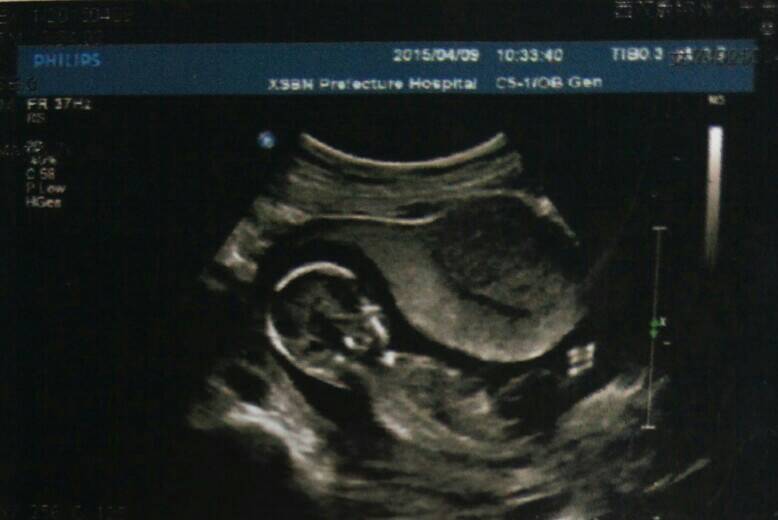

早上起来就肚子痛,也正好是第二次产检时间,去了医院就只量一个血压就告诉我可以了,我告诉医生肚子痛,她就叫我去照BC,BC医生更奇葩,等了2小时才照上,明明肚子痛告诉她还使劲按我肚子,有会我痛了叫起来了,BC医生面无表情,唉!那分钟委屈死了,不过看见宝宝的彩超,可爱的让我想流泪,真心不容易呀!每天睡不好,还便秘,还好没有孕吐,我对所有宝妈致敬!

你好根据你的描述便秘与活动少,肠蠕动慢有关,可以吃蔬菜,香蕉,苹果,适当喝水,偶尔腹痛可能与你睡觉姿势不好,或受凉有关,超生波检查胎儿发育正常可以无需处理。建议定期产检